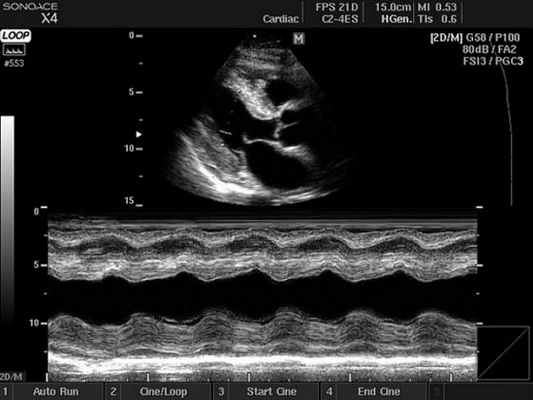

Ультразвуковое исследование сердца в основном используется для получения двухмерного изображения этого органа и близлежащих магистральных сосудов. А также с помощью этой методики можно оценить скорость и направление кровотока, что требует применение эффекта Допплера. В зависимости от того, как обрабатывается и отображается на мониторе эхо-сигнал, различают следующие режимы ЭхоКГ:

- Двухмерный (2D режим). На монитор выводится изображение сердца в разрезе (в двух измерениях). Данный способ является основным при визуализации этого органа, позволяет детально рассмотреть анатомические отклонения и аномальные движения миокарда, клапанов.

- М-режим (M-mode). Это «усеченный» вариант предыдущего, при котором используется для анализа только одномерное изображение. Основное внимание уделяется одной из линий 2D трассировки, что позволяет более детально исследовать движения створок клапанов и сердечной мышцы.